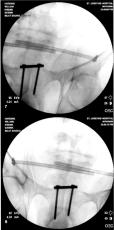

Screw Removed from Right Ankle

As can be noted in many of the right ankle x-rays, there was a screw that Dr. Keller placed in Liam’s lower right fibula which was

supposed to be through the plate in the fibula, but instead Dr. Keller missed the plate and simply screwed it into the bone. In the

position that the screw was place it caused considerable pain for Liam and obstructed Liam’s normal foot motion. The images below

show Dr. Gottlieb correcting Dr. Keller’s mistake.